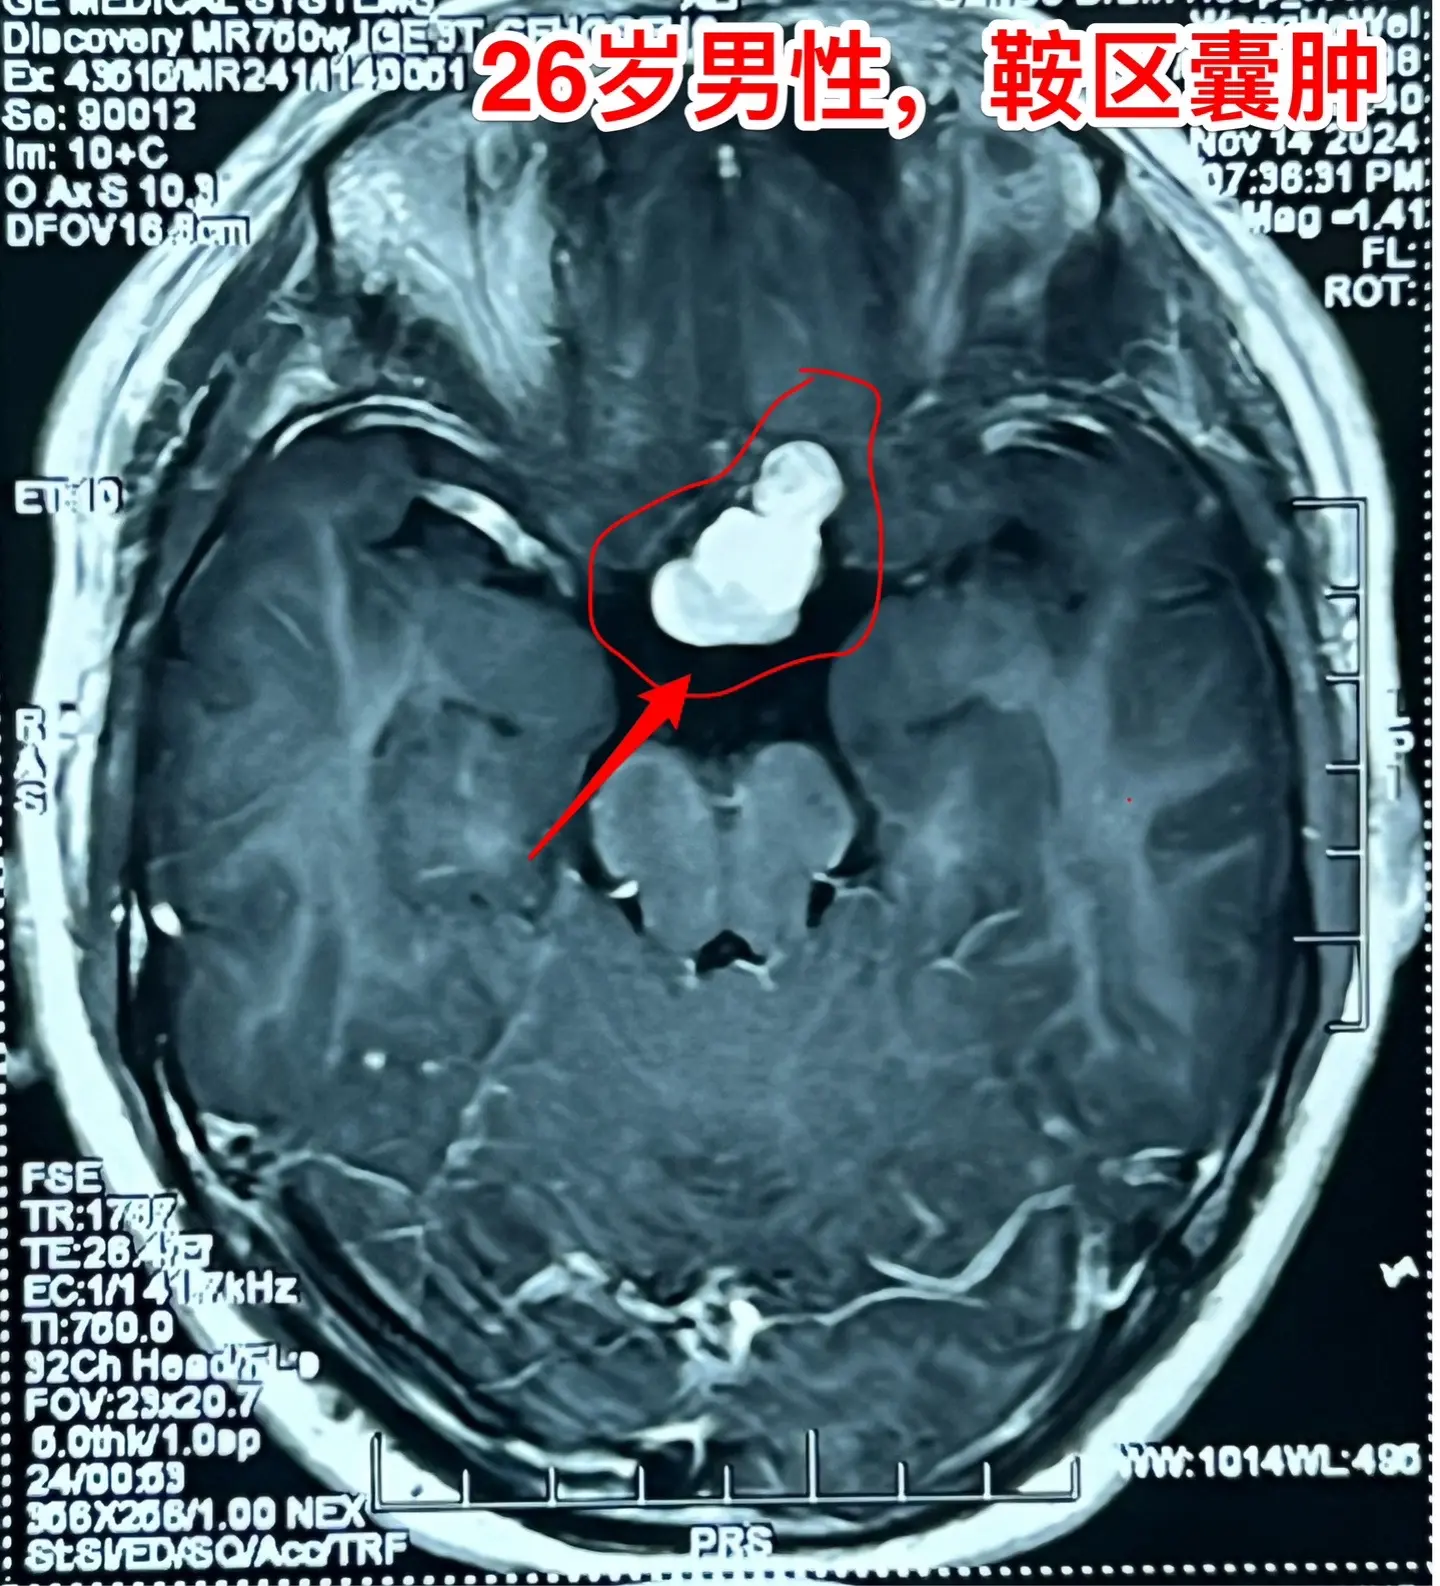

拉克氏囊肿的症状有时和颅咽管瘤是一样的。拉克氏囊肿不是真正的肿瘤,但是其发生的位置和颅咽管瘤很相似。通常情况下拉克氏囊肿的症状比较轻微,但是有的拉克氏囊肿体积大,对下丘脑-垂体的损害也很严重,产生明显的下丘脑-垂体功能障碍,同时也会压迫视神经产生视力下降,和颅咽管瘤产生的症状一样。 这个26岁的湖北孝感市小伙子有头痛、视力下降症状,化验显示也有垂体功能减退。所以有手术指征了。2024.11.22作了手术,将囊肿大部分切除,充分减压,尽可能地保留垂体柄和垂体的功能。